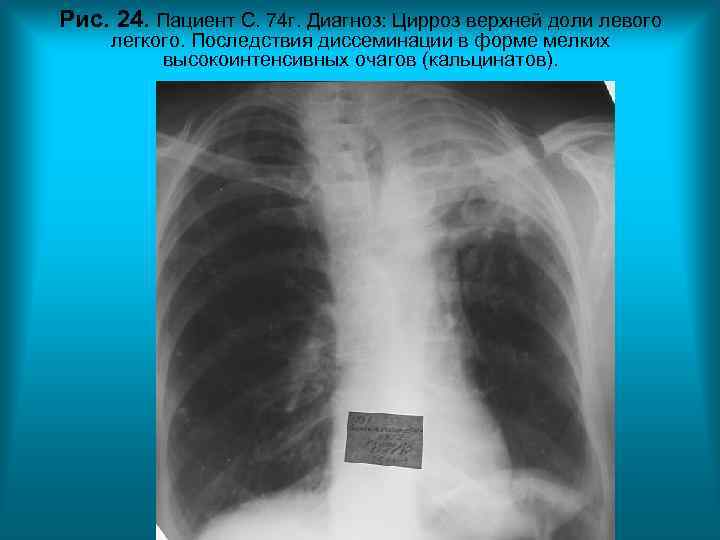

Рис. 24. Пациент С. 74 г. Диагноз: Цирроз верхней доли левого легкого. Последствия диссеминации в форме мелких высокоинтенсивных очагов (кальцинатов). Н. С. Воротынцева. С. С. Гольев Рентгенопульмонология